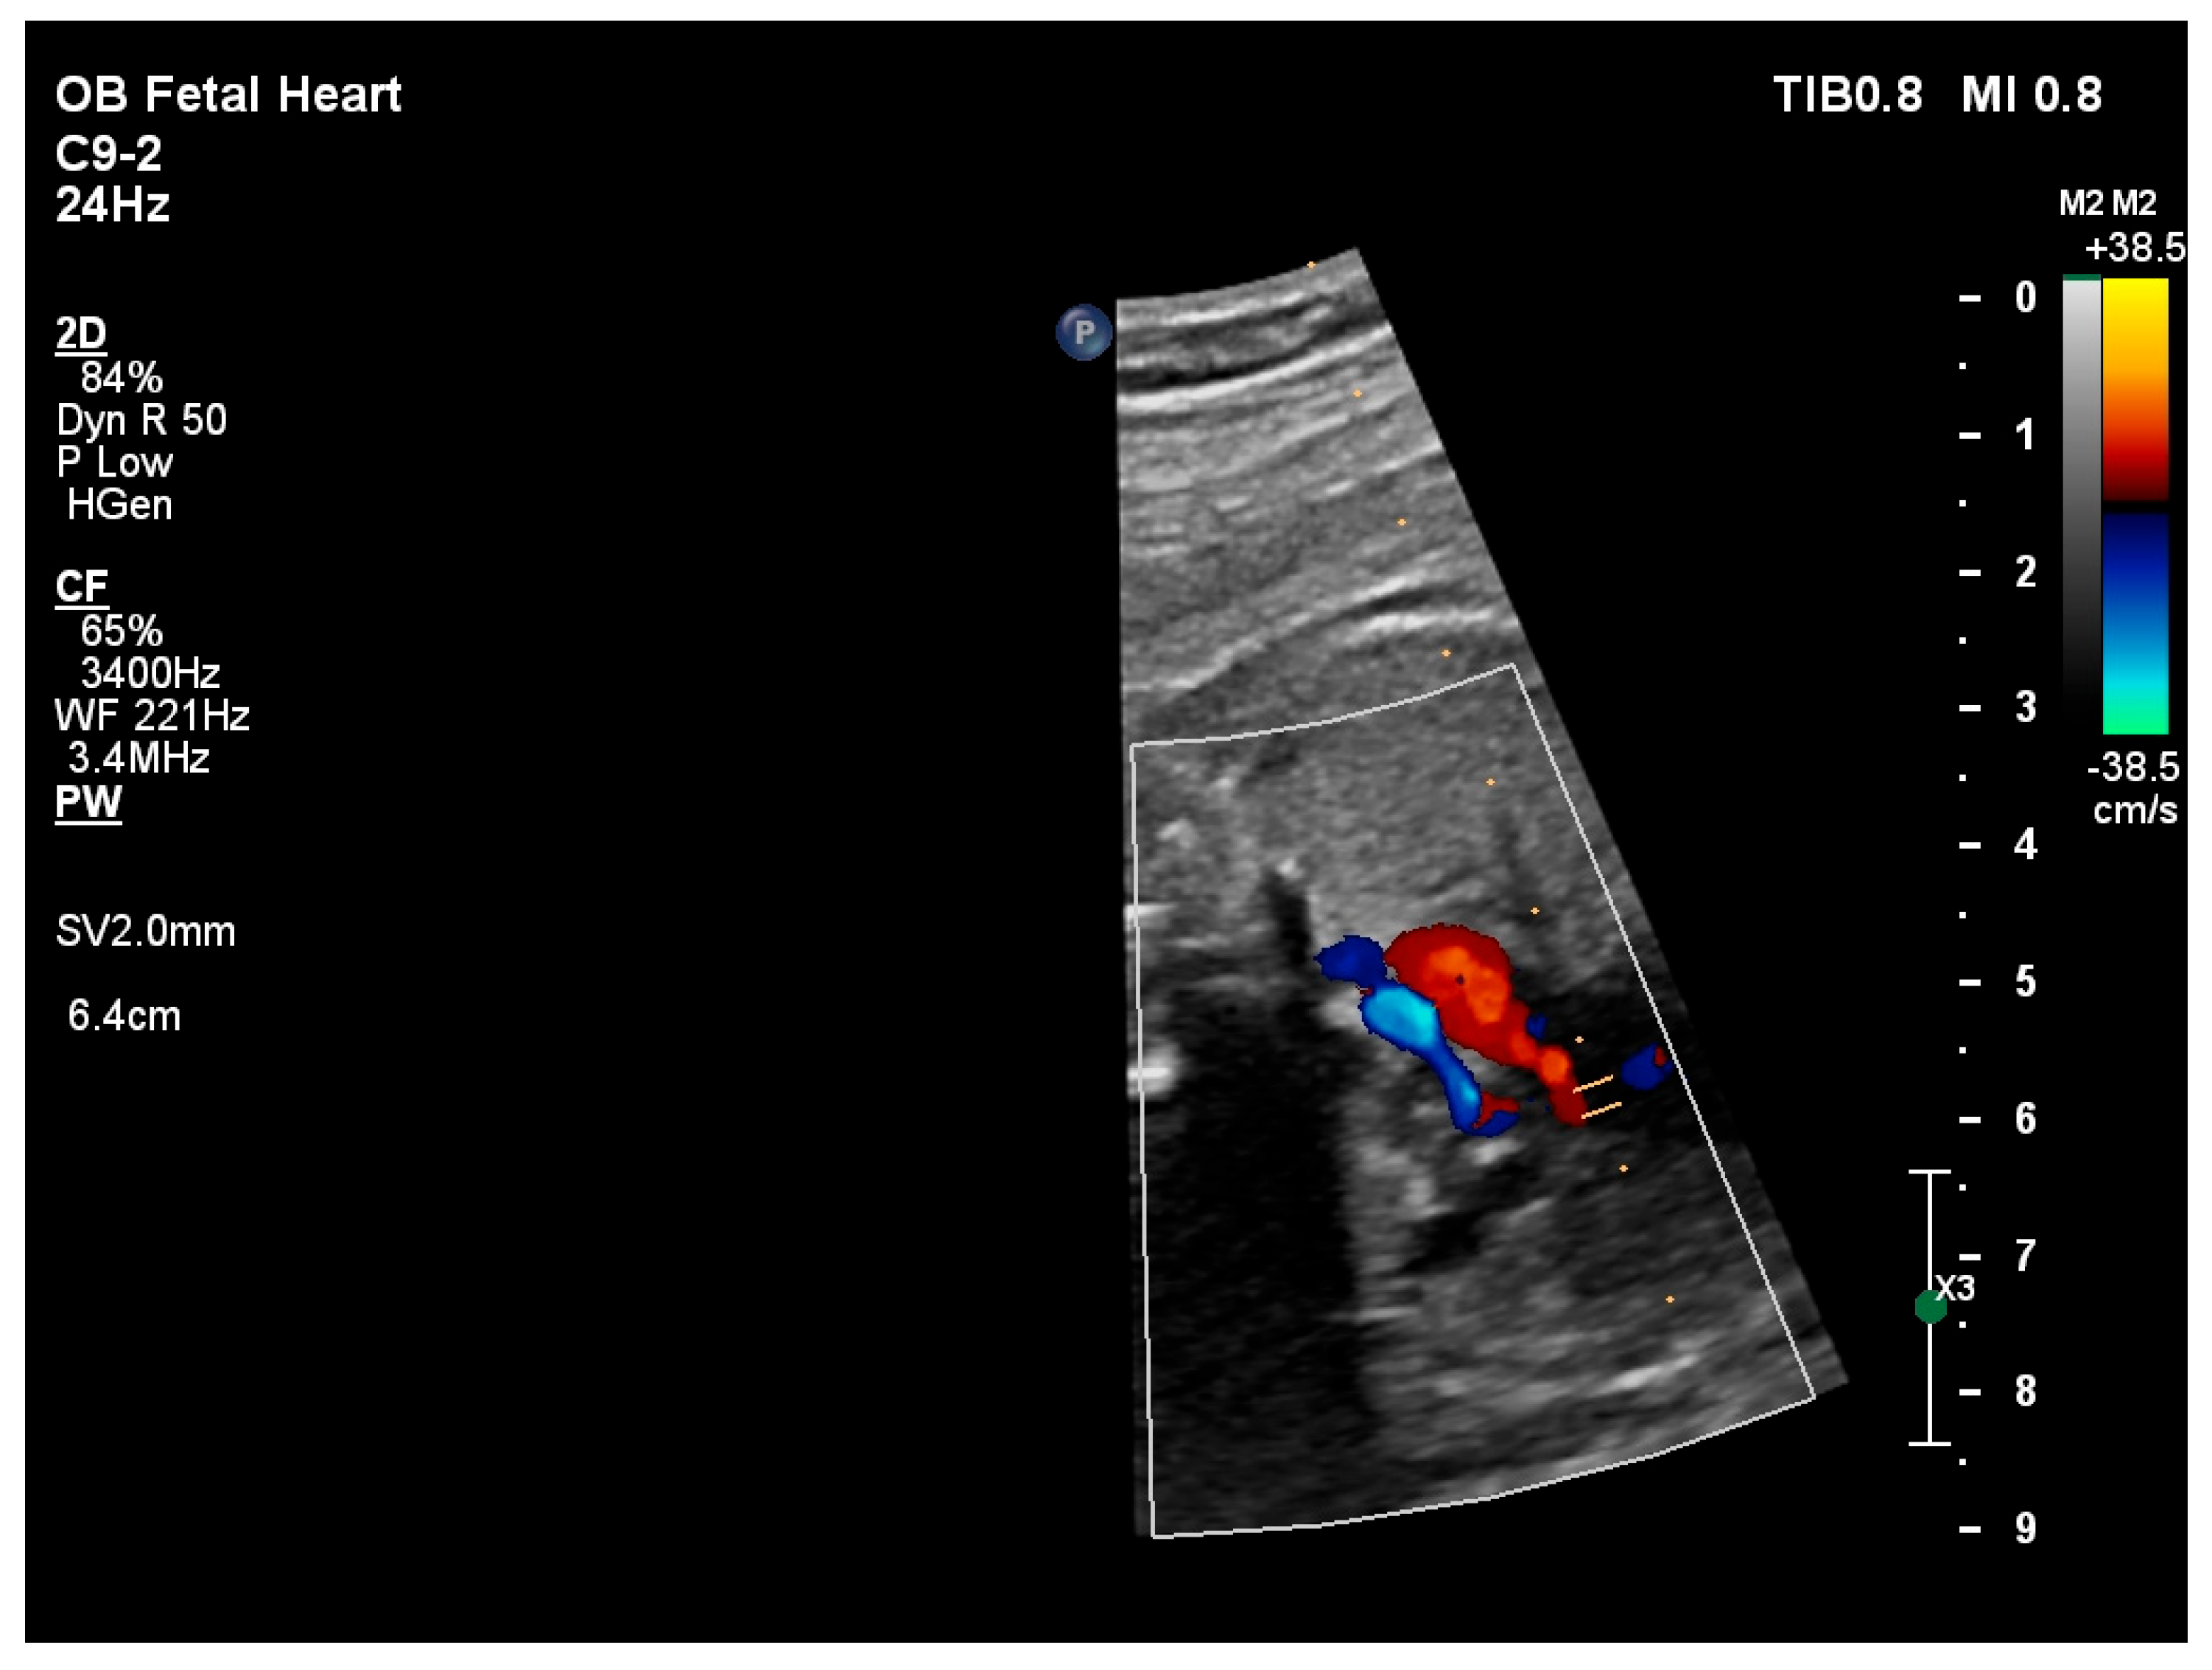

2.1. Prenatal Echocardiographic Findings

| Ventricular disproportion (TV/MV ratio) | ≥1.5 (Yes) | ≥1.5 (Yes) | ≥1.5 (Yes) | TV/MV ≥ 1.5 indicates significant ventricular disproportion |

| Mitral valve Z-score | −4.57 | −4.40 | −4.64 | Normal: −2 to +2; Z-score < −3 associated with unfavorable anatomy for primary biventricular repair |

| Biphasic transmitral inflow | Present | Present | Present | Biphasic pattern consistent with impaired LV relaxation |

| Aortic annulus Z-score | −3.36 | −3.30 | −3.28 | Normal: −2 to +2; Z-score < −3 indicates severe hypoplasia |

| Aortic isthmus Z-score | −3.46 | −3.43 | −3.40 | Z-score < −3 consistent with severe arch hypoplasia/coarctation |

| Endomyocardial fibroelastosis | Absent | Absent | Absent | Presence of EFE is an adverse predictor for biventricular repair |

| Restrictive atrial septal defect | No | No | No | Restriction suggested by high-velocity atrial shunt and LA hypertension |

| Apex-forming left ventricle | No | No | No | Apex-forming LV generally favors biventricular feasibility |

| LV peak global longitudinal strain (%) | −18.3 | −18.6 | −19.3 | Typical fetal LV pGLS ≈ −16% to −22% |